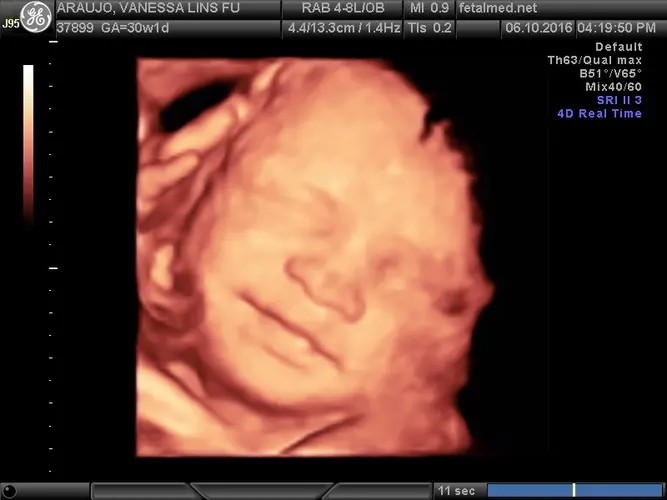

Seu pequeno já está bastante crescido e pesando aproximadamente 1,4 quilos! O desenvolvimento mais impressionante desta semana acontece no cérebro do seu bebê, que está passando por uma transformação fundamental. A superfície cerebral começa a formar os sulcos e circunvoluções característicos, criando aquele aspecto “enrugadinho” típico do cérebro humano. Essas dobrinhas não são apenas cosméticas – elas são essenciais para permitir que mais tecido nervoso se acomode no espaço limitado do crânio, maximizando a área disponível para as células cerebrais.

Os olhinhos do seu bebê já se abrem e fecham regularmente, e ele consegue perceber mudanças de luz através da parede abdominal. O útero não é um ambiente completamente escuro como muitos imaginam – dependendo da iluminação externa, seu bebê pode experimentar diferentes intensidades de luz. As unhas dos pés estão crescendo, o cabelo está se desenvolvendo, e o lanugo (aquela penugem fina) está começando a desaparecer, permanecendo apenas nas costas e ombros.